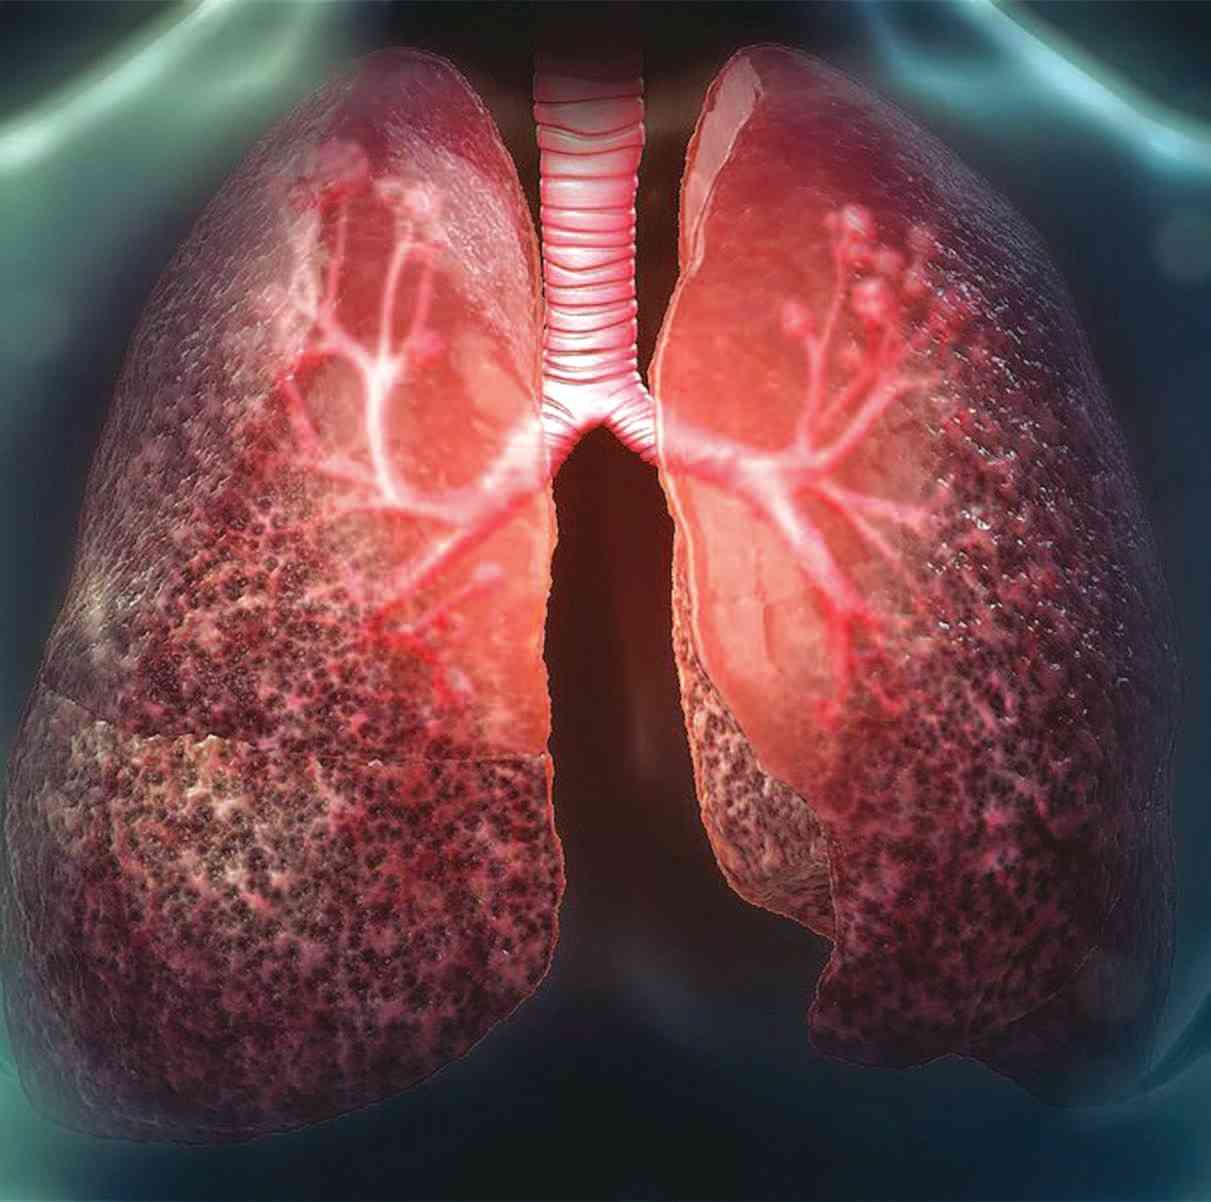

وأشارت إلى أن ذلك «يؤدي إلى إفرازات مخاطية، تتسبب في انسداد الشعب الهوائية في الرئة، وتؤدي إلى صعوبة التنفس وعدوى في الجهاز التنفسي قد تهدد الحياة، وغالباً ما يموت المرضى قبل سن الأربعينيات، لأن المخاط يؤدي إلى انسداد الرئتين والإضرار بهما».